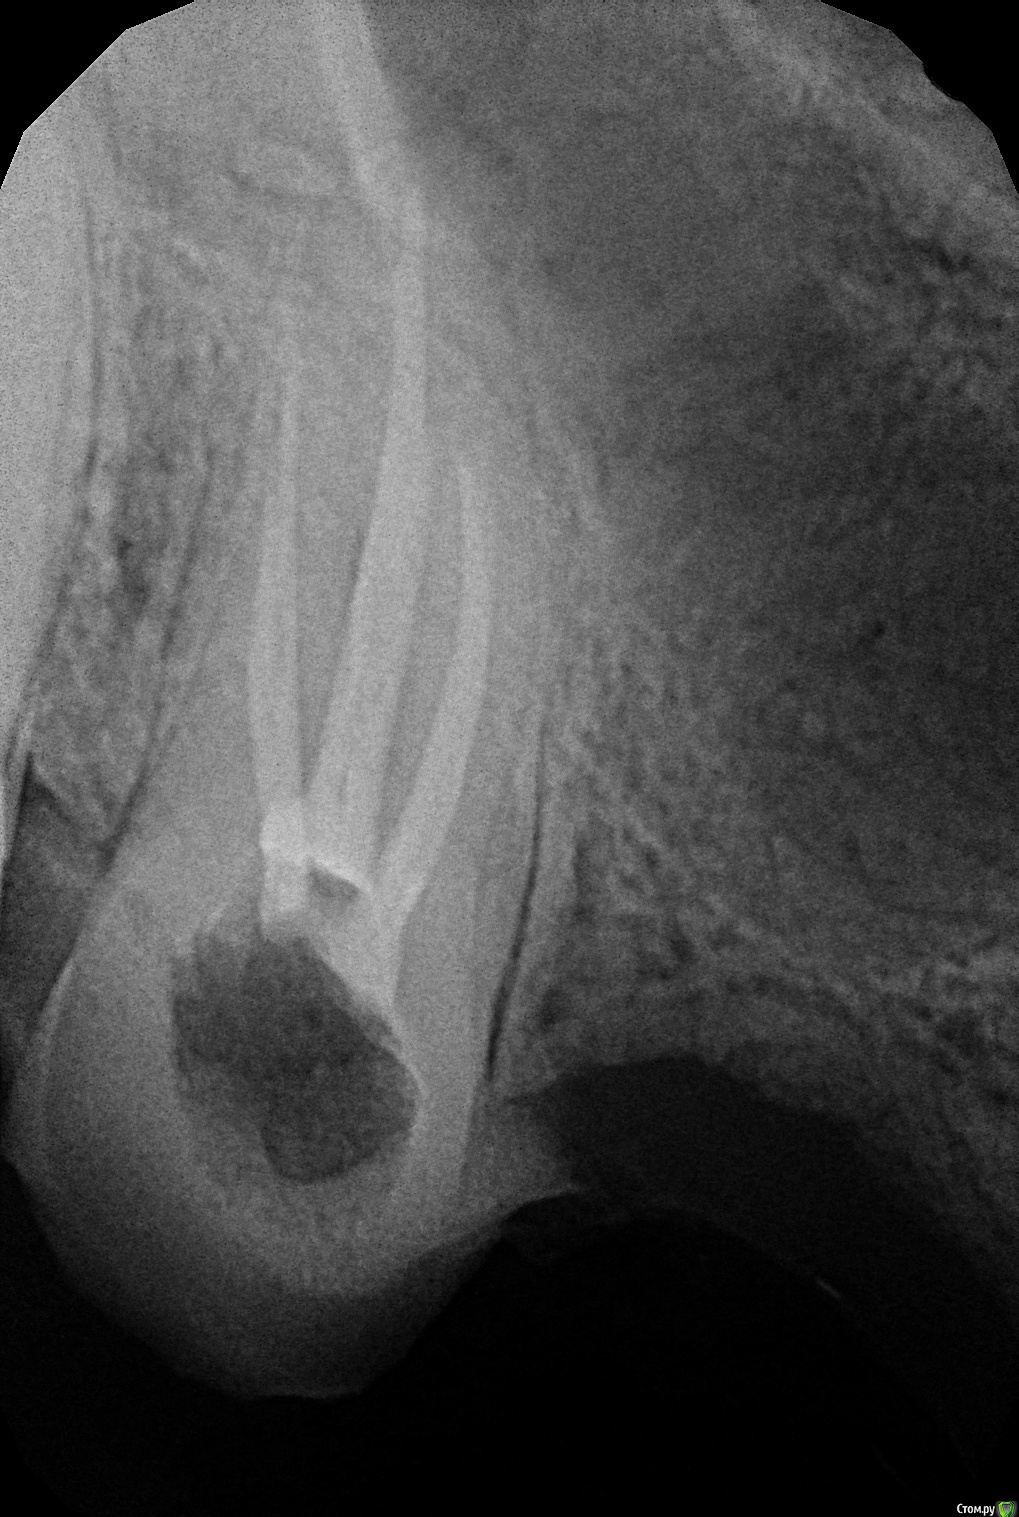

ARislanV Опубликовано 2 июля, 2016 Автор Поделиться Опубликовано 2 июля, 2016 давайте снимокВот снимок после пломбирования корней. Щечные короткие, небный более или менее. Ссылка на комментарий

ARislanV Опубликовано 2 июля, 2016 Автор Поделиться Опубликовано 2 июля, 2016 короче чем нибудь (прости меня господи) сносите десну с небной стороны хоть бором, или скальпелем, как вам удобнее или доступнее будет, потом полученный результат зафиксируйте временной пломбой, композитом, бисакрилом. суть в том, чтоб создать механический барьер для роста десны "обратно".жуть . Я БЫ УДАЛИЛ ЭТИ ОСТАТКИ БЕЗ ВАРИАНТОВУ меня был тример фирмы NTi беленький такой, по пробывал с ним. Убрал по периметру десну на 1.5 мм и все залил Силидонтом. 1 Ссылка на комментарий